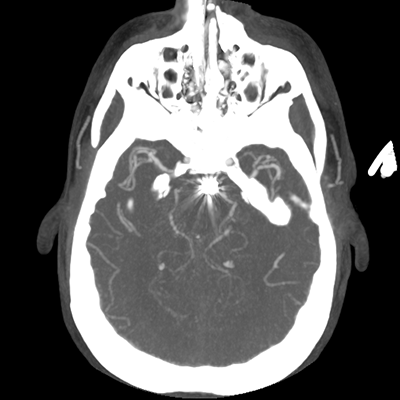

The patient goes down to CT. The following images are obtained. The subdural fluid collection is stable, as is the ventricular caliber.

CTA head (MIP)

Starting with the non-contrast head CT, we can appreciate that there's actually not much residual subarachnoid blood at all; it's essentially all resorbed already (and cleared through the EVD). The ventricular caliber is stable. With the CTA head (for convenience's sake, the MIPs were shown), it's subtle, but we can see that the PCAs on each side are not as smooth and regular. The right MCA, starting at the bifurcation, also becomes narrower. This is [radiographic] vasospasm. Now, looking at the CT perfusion-- specifically, the Tmax (MTT) map that were selected-- there's clearly some abnormality within the bilateral cerebellar hemispheres and occipital lobes. Not a lot, but it's there. Delving further into this map, we can appreciate that the areas of abnormality are mainly green, signifying that these areas have Tmax > 6 seconds. This is the threshold that is specific, not sensitive, for vasospasm.

Putting this all together, we have thus identified radiographic vasospasm with the vessel imaging, with perfusion abnormalities that are concordant with it. Does the area of vasospasm and hypoperfusion correlate with the patient's clinical exam?

Yes! It does. The patient had a decline in level of consciousness with diffuse loss of motor function. This does correlate to the basilar territory. (Alternatively, bilateral MCA vasospasm could also be responsible, reminding us that a decline in consciousness could technically be focal/multifocal.) Thus, we can say that this patient does have clinical vasospasm. Whether this will develop into irreversible DCI remains to be seen; at least, the non-contrast head CT and the other portions of the CT perfusion (not shown) currently don't [yet] suggest infarction.